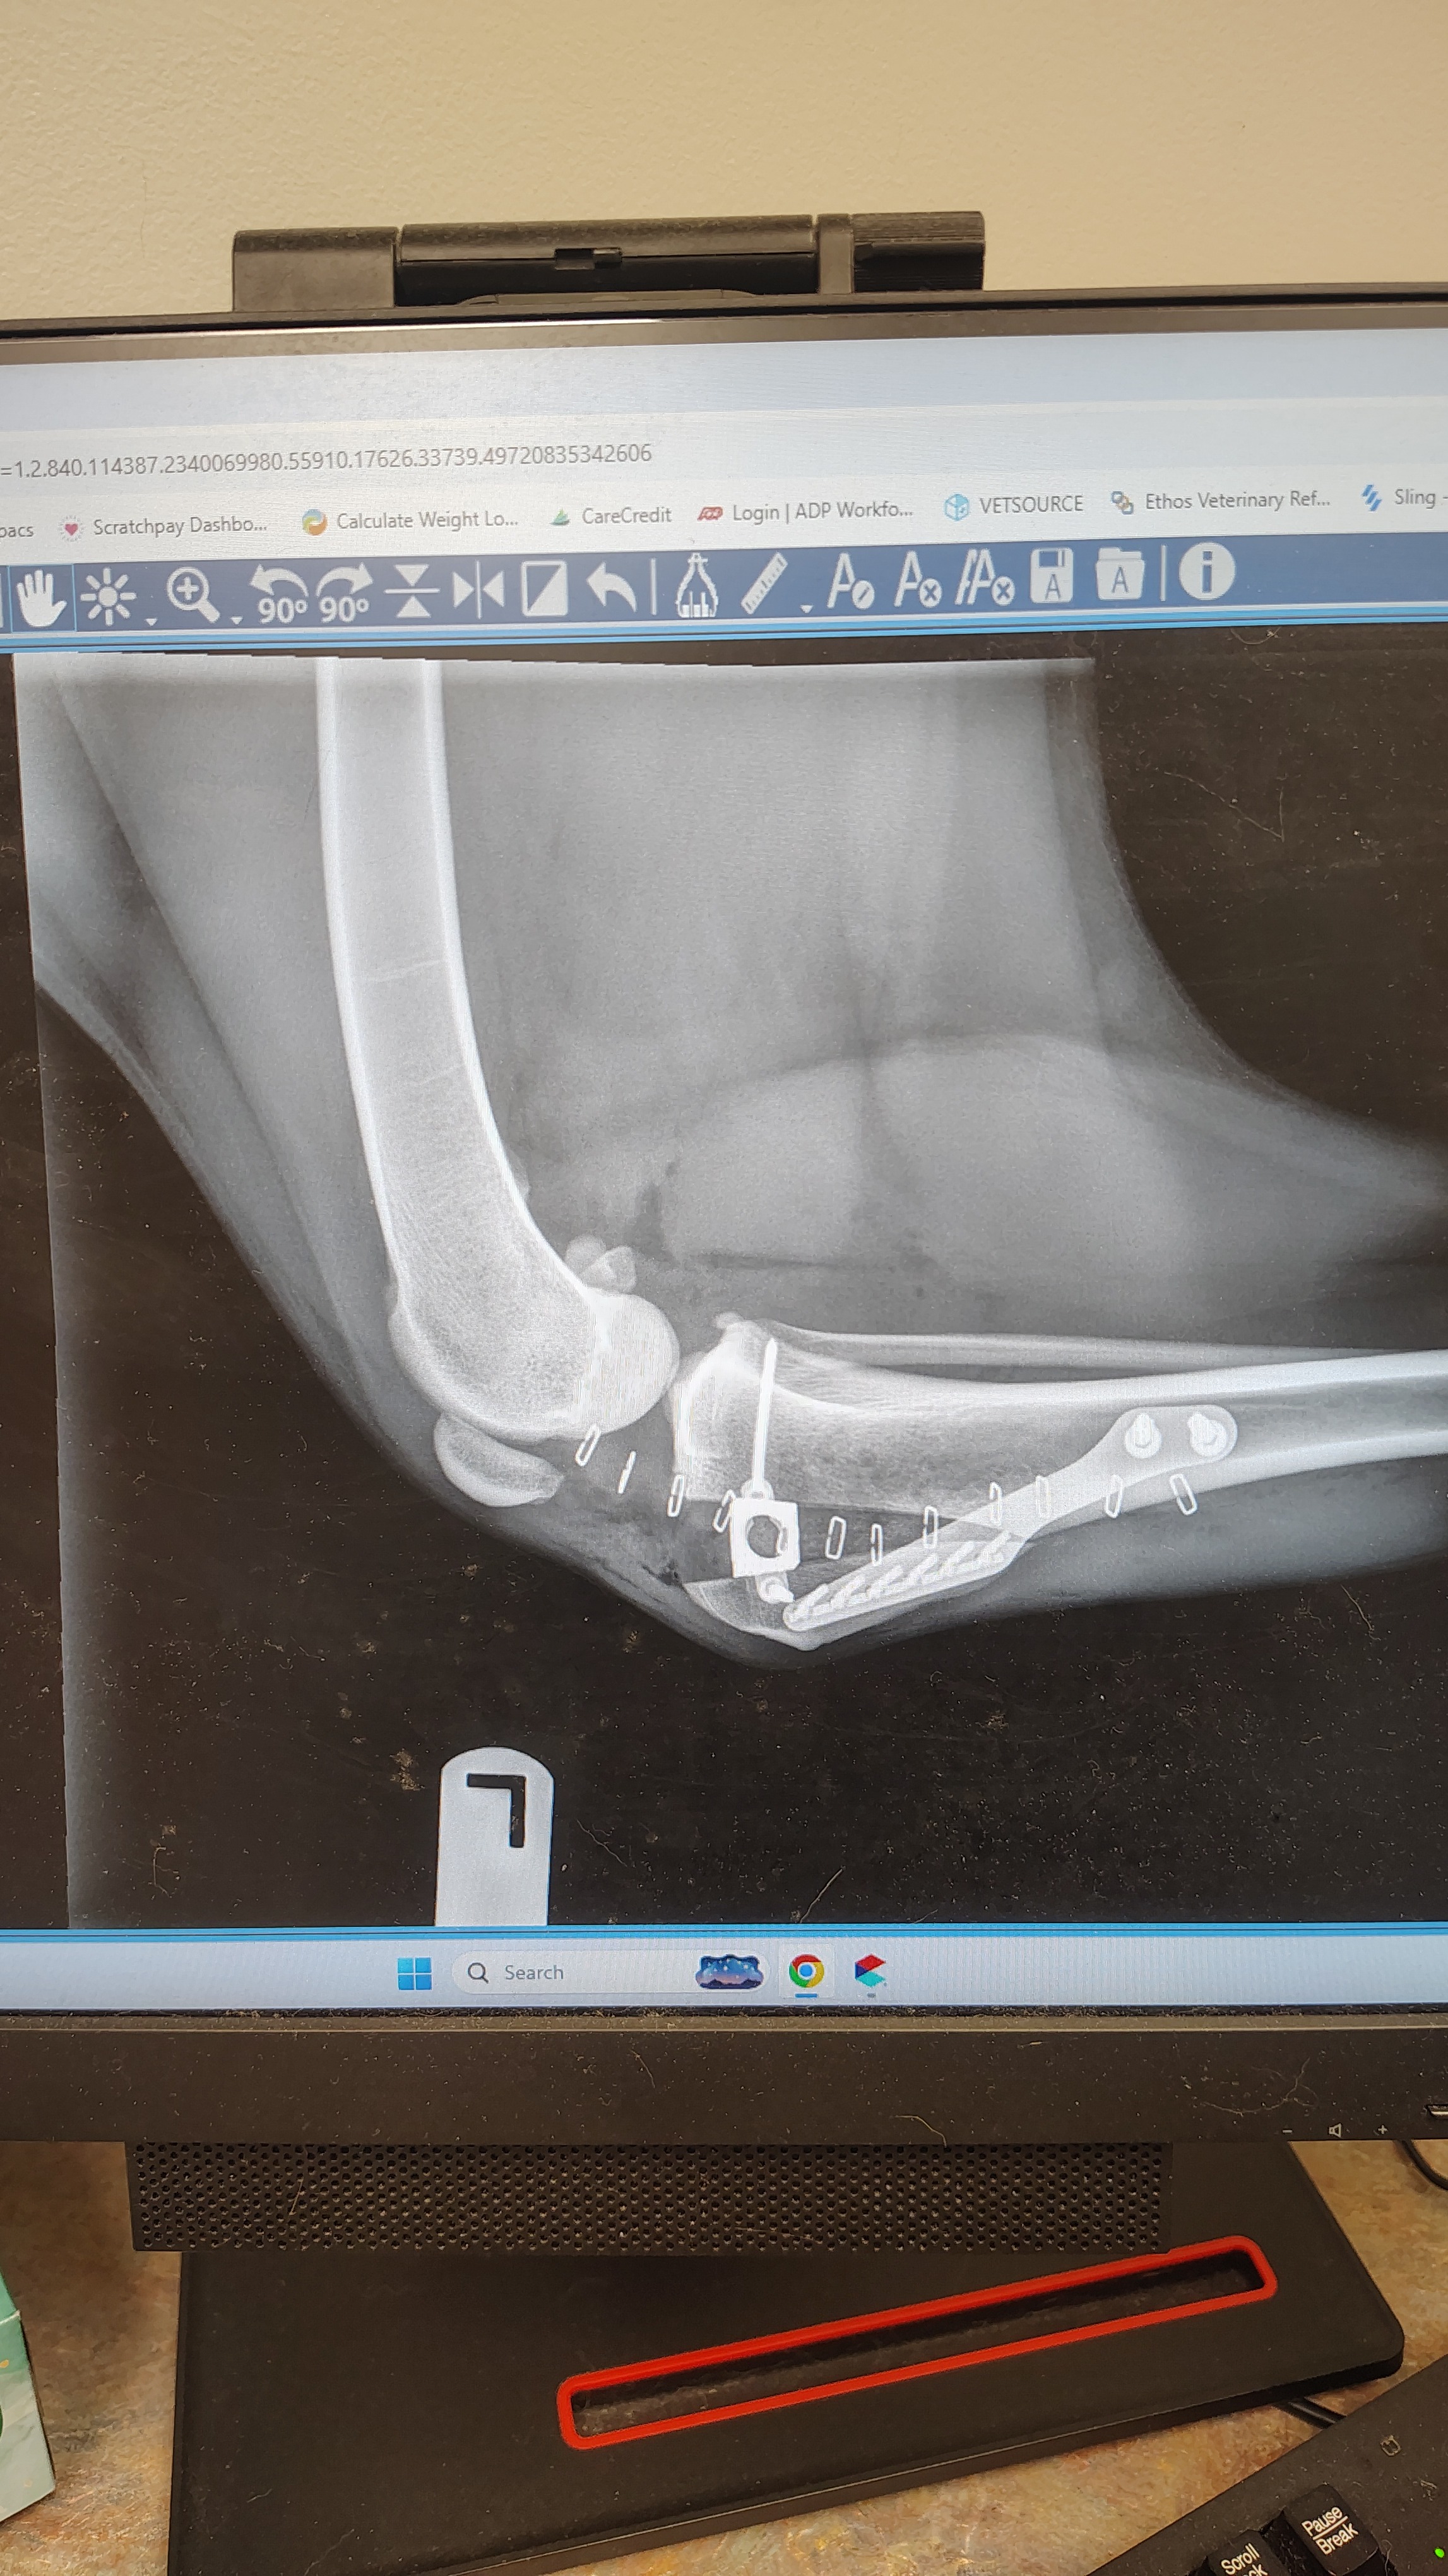

Just six weeks ago, Tyson tore his ACL and underwent a major TTA (Tibial Tuberosity Advancement) surgery on his left leg. We spent just under $10,000 to get him fixed up, draining our resources to make sure he could live pain-free again. We were right in the middle of his recovery when the absolute worst thing happened—his right leg let go. His left leg is still quite weak with basically all of the muscle mass gone. That left his other leg to hold all the weight.